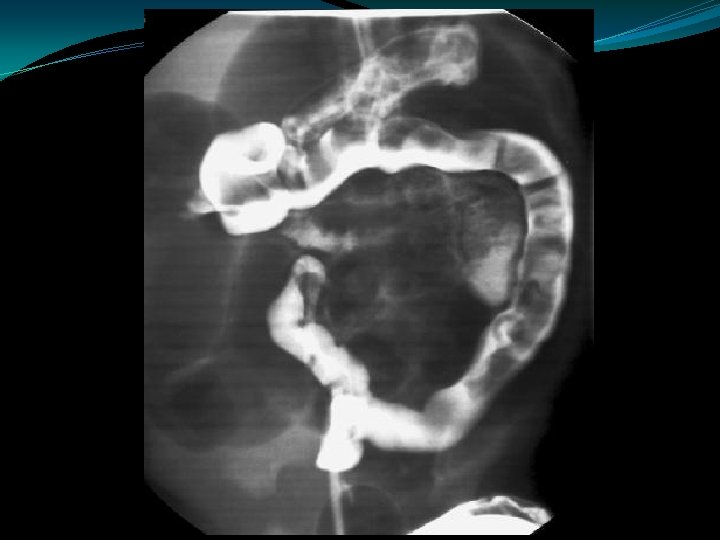

Meconium Ileus �Contrast enema: �Small colon �Filled with pellet-like meconium when contrast extends to IC valve �Contrast can wash out the obstructing plugs and meconium plugs �The diagnosis of CF should be ruled-out

Meconium Plug Syndrome �Diagnosis of exclusion �Probably same as "small left colon" syndrome �Transient disorder due to functional immaturity of colon �Common in IDM, premies, PIH, Mg Rx �Infants with CF may present with mec plugs, although mec ileus most common � 10 -30% may have Hirschsprungs also